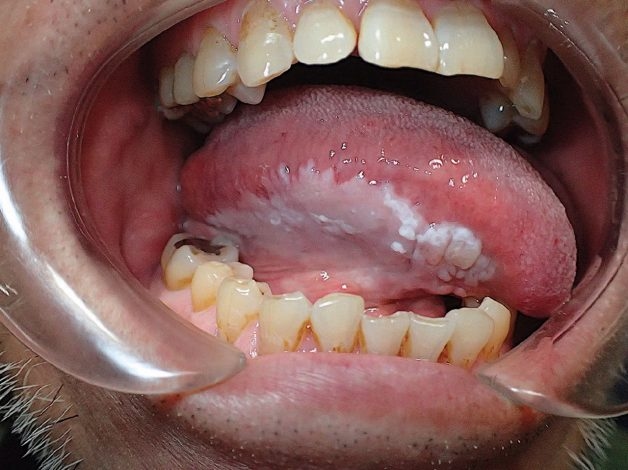

– Với bạch sản dạng lông, triệu chứng thường gặp là lông xuất hiện, có những mảng trắng mờ dạng nếp gấp hoặc đường lằn ở hai bên đầu lưỡi.

Với bạch sản dạng lông, triệu chứng thường gặp là lông xuất hiện, có những mảng trắng mờ dạng nếp gấp hoặc đường lằn ở hai bên đầu lưỡi

Bên cạnh đó, một dạng bệnh bạch sản là bạch sản dạng lông gây ra bởi virus Epstein-Barr (EBV). Khi đã xâm nhập được vào cơ thể, loại virus này sẽ ở trong cơ thể vĩnh viễn và gây nên những vét loét và phát triển bệnh bất cứ lúc nào. Đối tượng có tỷ lệ cao phát bệnh này là người nhiễm HIV hoặc có vấn đề về hệ miễn dịch.